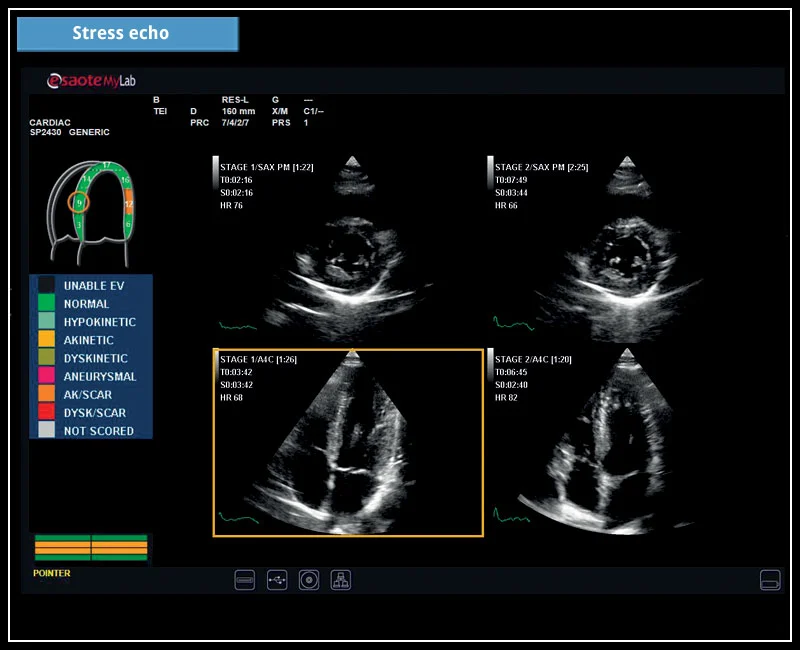

MyLab™X5 - Stress echo

MyLab™X5 - Stress echo

MyLab™X6 - Stress echo

MyLab™X6 - Stress echo

MyLab™X7 - Stress echo

MyLab™X7 - Stress echo

MyLab™Omega - Stress Echo

MyLab™Omega - Stress Echo